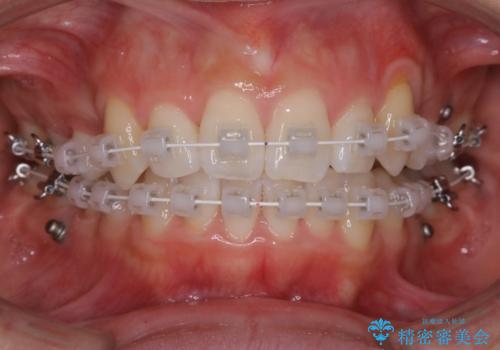

- ワイヤー矯正

左側のかみ合わせは、歯1本分かみ合わせが前にずれていました。上顎左右の奥歯を2本抜歯しています。

下顎は、歯の側面を少し削ることで歯並びを整えました。

上顎と下顎の奥歯の抜歯(計4本)を行う治療方法もありますが、口元のバランスのことも考え、上顎の抜歯のみで、治療を行いました。